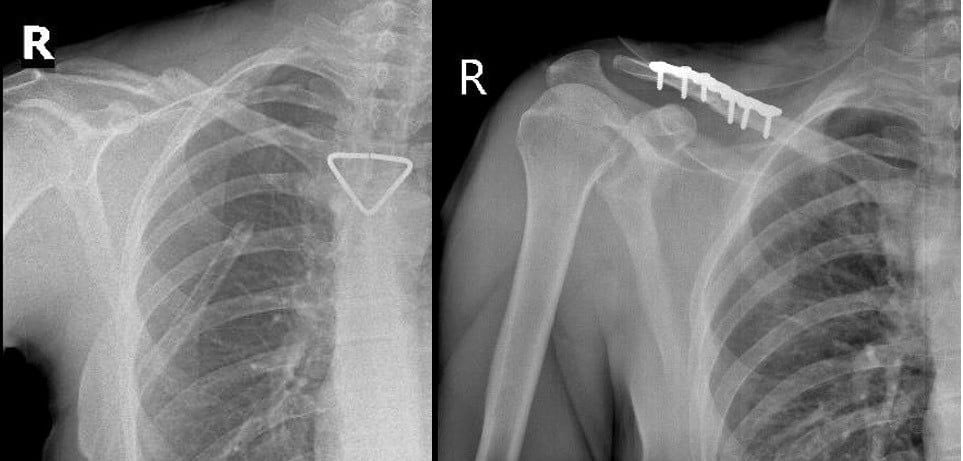

Phim CT scan lồng ngực sáng ngày nhập viện ghi nhận tràn khí màng phổi phải lượng nhiều

Ngay khi tiếp nhận, các bác sĩ đã khẩn trương thực hiện CT scan lồng ngực, mạch máu khẩn cấp. Kết quả cho thấy người bệnh bị tràn khí màng phổi phải lượng nhiều gây chèn ép phổi, gãy cung bên xương sườn 2, 3, 4 phải và gãy phức tạp 1/3 giữa xương đòn phải, di lệch nhiều kèm mảnh rời.